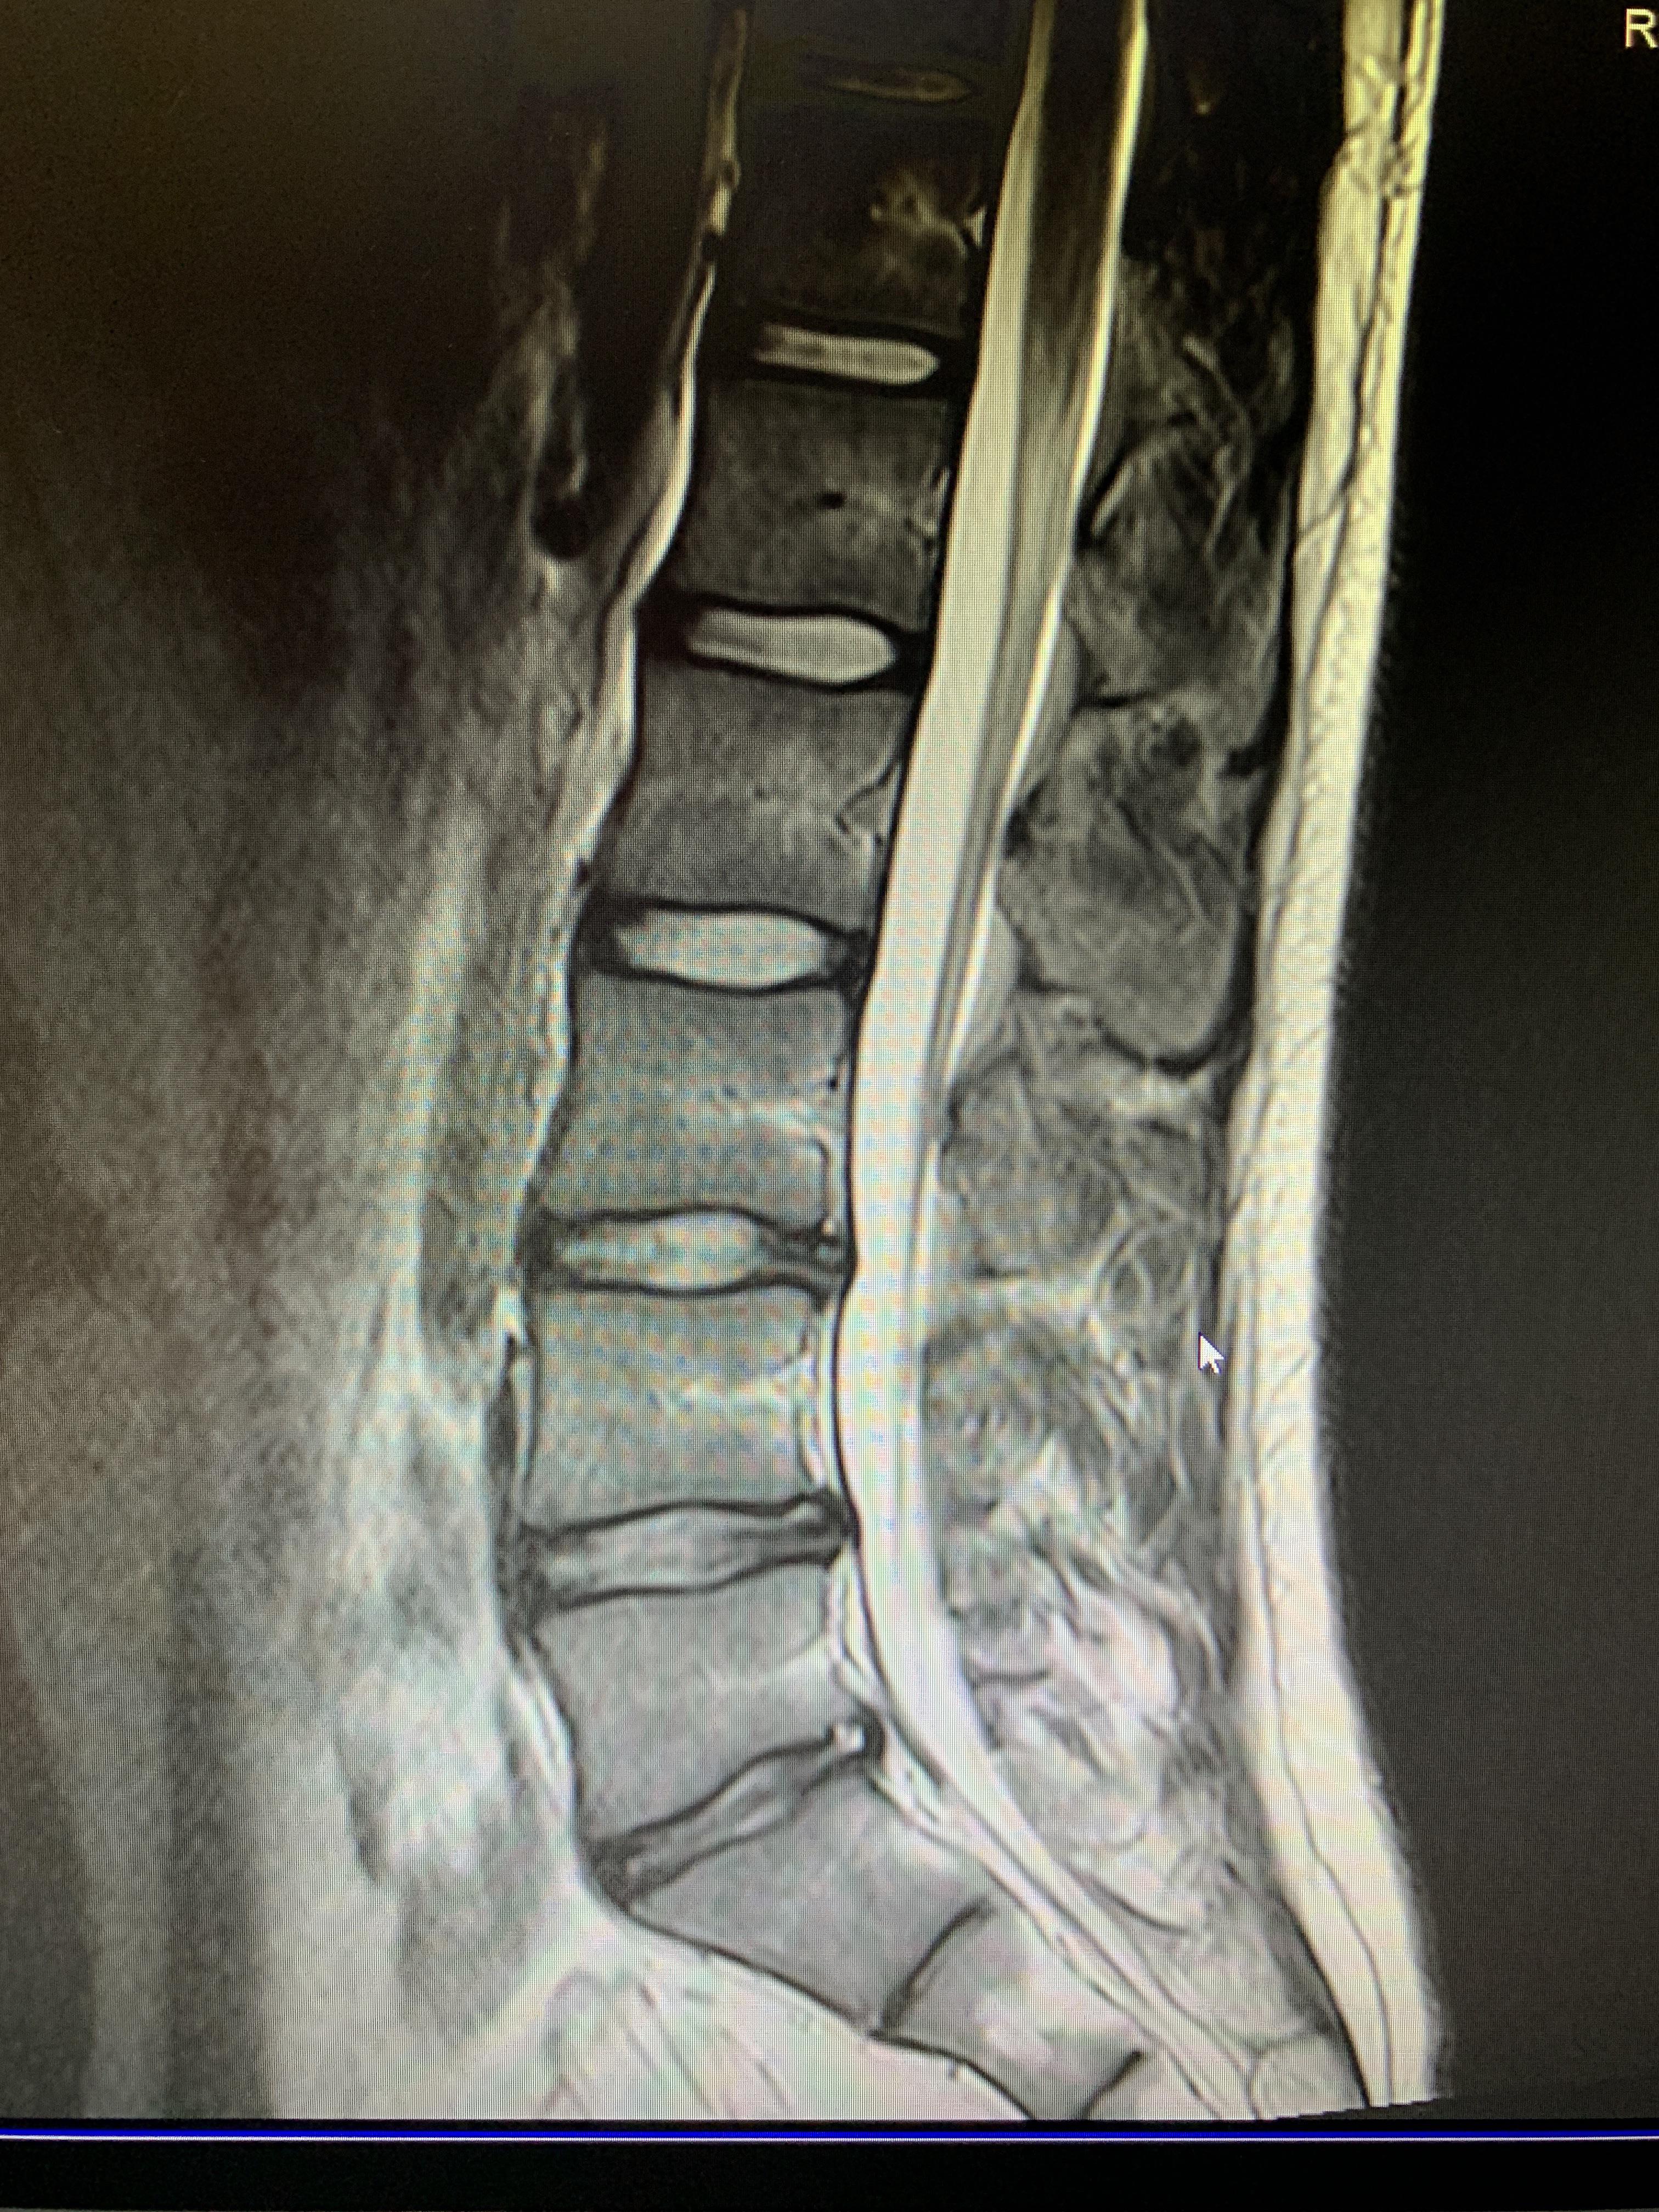

What Is Lumbar Mri . What is a lumbar spine mri? An mri scanner is a large tube that contains. A lumbar mri is a noninvasive procedure that doctors use to help diagnose lower back pain, plan back surgery, or monitor progressive medical conditions,. The five lumbar vertebrae from l1 to l5; To help you prepare, here is a look at the details behind an mri of the lumbar region, as well as a brief description of what you can see and why doctors order mris for this location. A lumbar spine mri focuses on the lower part of the spinal column, specifically: You'll lie on a motorised bed that's moved inside the scanner. Get in touchall inclusive pricing Magnetic resonance imaging (mri) is a type of scan that uses strong magnetic fields and radio waves to produce detailed images of the inside of the body. If your doctor has recommended an mri of your lumbar spine, you might be wondering what this imaging test shows. You'll enter the scanner either. How to read a lumbar mri. An mri scanner is a short cylinder that's open at both ends. For the lumbar spine, an mri provides clear images of bones, intervertebral discs, nerves, and surrounding soft tissues, allowing for accurate identification of potential problems. Magnetic resonance imaging (mri) uses radio waves and a powerful magnetic field to create detailed images of the body’s soft tissues, organs, muscles and structures.

What Is Lumbar Mri Magnetic resonance imaging (mri) uses radio waves and a powerful magnetic field to create detailed images of the body’s soft tissues, organs, muscles and structures. Magnetic resonance imaging (mri) uses radio waves and a powerful magnetic field to create detailed images of the body’s soft tissues, organs, muscles and structures. Get in touchall inclusive pricing An mri scanner is a short cylinder that's open at both ends. What is a lumbar spine mri? Magnetic resonance imaging (mri) is a type of scan that uses strong magnetic fields and radio waves to produce detailed images of the inside of the body. An mri scanner is a large tube that contains. If your doctor has recommended an mri of your lumbar spine, you might be wondering what this imaging test shows. You'll enter the scanner either. To help you prepare, here is a look at the details behind an mri of the lumbar region, as well as a brief description of what you can see and why doctors order mris for this location. You'll lie on a motorised bed that's moved inside the scanner. For the lumbar spine, an mri provides clear images of bones, intervertebral discs, nerves, and surrounding soft tissues, allowing for accurate identification of potential problems. A lumbar mri is a noninvasive procedure that doctors use to help diagnose lower back pain, plan back surgery, or monitor progressive medical conditions,. A lumbar spine mri focuses on the lower part of the spinal column, specifically: The five lumbar vertebrae from l1 to l5; How to read a lumbar mri.